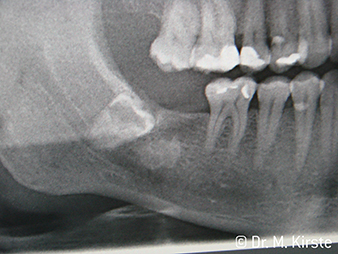

Por primera vez, los instrumentos de transmisión WS-91 y WS-91 L G combinan las ventajas de las piezas de mano y los contra-ángulos quirúrgicos (Figura 1). Al haber ampliado el ángulo hacia el panel frontal entre la zona del mango y el eje de la fresa, se permite un buen acceso a la dentadura tanto bucal como oclusal (Figura 4). Los dientes desplazados pueden extraerse fácilmente (Figuras 6 y 7). Además, el doctor percibe mucho mejor el campo de operación que con los instrumentos disponibles anteriormente. A este respecto, el Dr. Mario Kirste de Fráncfort del Óder (Alemania) comenta: «Cuando giro ligeramente el cabezal del contra-ángulo, puedo trabajar de forma rápida y segura en la zona retromolar. El instrumento tiene el potencial de agrupar las diferentes posiciones necesarias tanto para los usuario de contra-ángulos como los de piezas de mano». (Figuras 2-5).